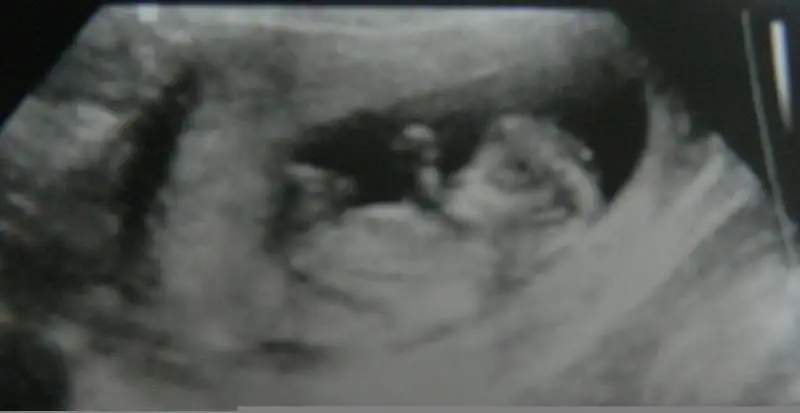

11+3 haftalığz burda dr o zaman bisey demedi ama bugün erkeğe benzer bisey göremedim kıza daha yakn dedi tekrar bakın bakalm ben hala erkek hissediyorum 3 hafta sonra netlesecek bakalm yorum bekliyorum anlayan arkadaslardan

Eklentiler

• $20131226_170107-1.webp

6,2 KB · Görüntüleme: 67